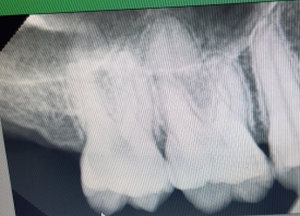

Разошлось мнение двух врачей: одна считает, что кариес на шестнадцатом есть, вторая, что его нет. На рентгене, на шестнадцатом виден темный участок, то есть, скорее кариес есть, чем его нет.

С вашей точки зрения он скорее есть, чем его нет? (речь идет не о поверхностном кариесе, который на рентгене нельзя увидеть, а о более глубоком: среднем или глубоком). Снимок был сделан до лечения.

На снимке в области семнадцатого и двадцать шестого зуба, под пломбой, наблюдается полость, которая неграмотно препарирована перед установкой пломбы, чувствительность и некий дискомфорт при надкусывании или пережевывании твердой пищи связано именно с этим. Что касается шестнадцатого зуба, я считаю, что полость имеется, но все-таки необходим еще и очный прием.